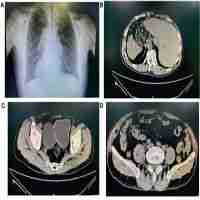

Lung cancer in situs inversus totalis (SIT) - a case report Rak płuca w zespole odwrócenia trzewi - opis przypadku

| Abstract | A case of a 69-year-old patient with bronchogenic large cell cancer of the left lung and metastatic tumor in the right suprarenal gland associated with situs inversus totalis (SIT) is presented. The patient underwent left thoracotomy and laparoscopy with the option of adjuvant chemotherapy afterwards. The SIT diagnosis was based on bronchofiberoscopy, contrast enhanced chest computed tomography and echocardiography as well. At the time of both operations the mirror image anatomy was confirmed. This is the second SIT case treated |